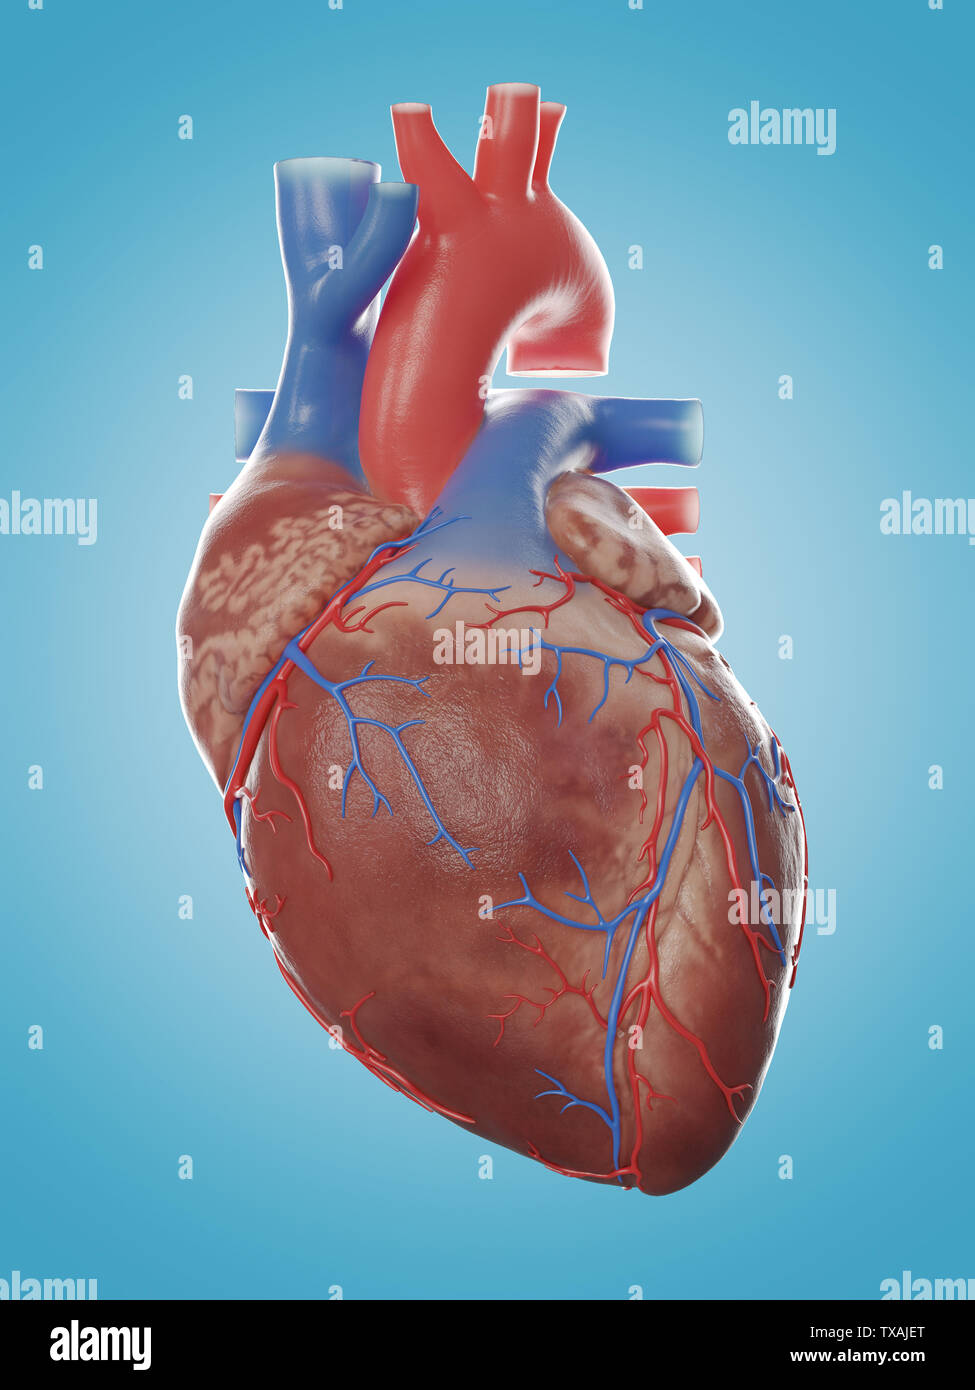

Human Heart 3D stock vector. Image of doodle, organ, conceptual - 43760249

Human Heart Drawing Outline at GetDrawings | Free download  3d anatomy human heart

Human Heart Sketchbook study by bluesytealyren on DeviantArt | Human heart drawing, Anatomical  3d human heart

3d human heart  Animated Realistic Human Heart - Medically 3D asset

Animated Realistic Human Heart - Medically 3D asset  Zygote::3D Heart Model | Medically Accurate | Human Anatomy

Zygote::3D Heart Model | Medically Accurate | Human Anatomy  Zygote::Solid 3D Human Heart Model

Zygote::Solid 3D Human Heart Model  3D human heart anatomy model - TurboSquid 1283134

3D human heart anatomy model - TurboSquid 1283134  anatomy human heart 3d c4d

anatomy human heart 3d c4d  Modeled human heart section 3D model - TurboSquid 1657004

Modeled human heart section 3D model - TurboSquid 1657004  Heart by Rustamova on @DeviantArt | Anatomical heart art, Anatomy art, Heart drawing

Heart by Rustamova on @DeviantArt | Anatomical heart art, Anatomy art, Heart drawing  3d human heart

3d human heart  Human Heart Pencil Drawing at GetDrawings | Free download

3d human heart  3d human heart

3d human heart  3d human heart anatomy model